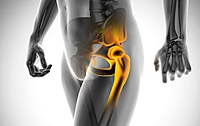

관절 부위의 연골이 닳아 고관절이 손상되는 질환입니다. 대퇴골두 무혈성 괴사, 비구이형성증, 선천성 고관절 탈구 등이 원인일 수 있습니다.

7. 고관절 골절

골밀도가 낮아지는 60대에 주로 발생하며, 고관절 골절 후에는 삶의 질이 크게 저하됩니다. 사망률도 높아져 심각한 질환입니다.